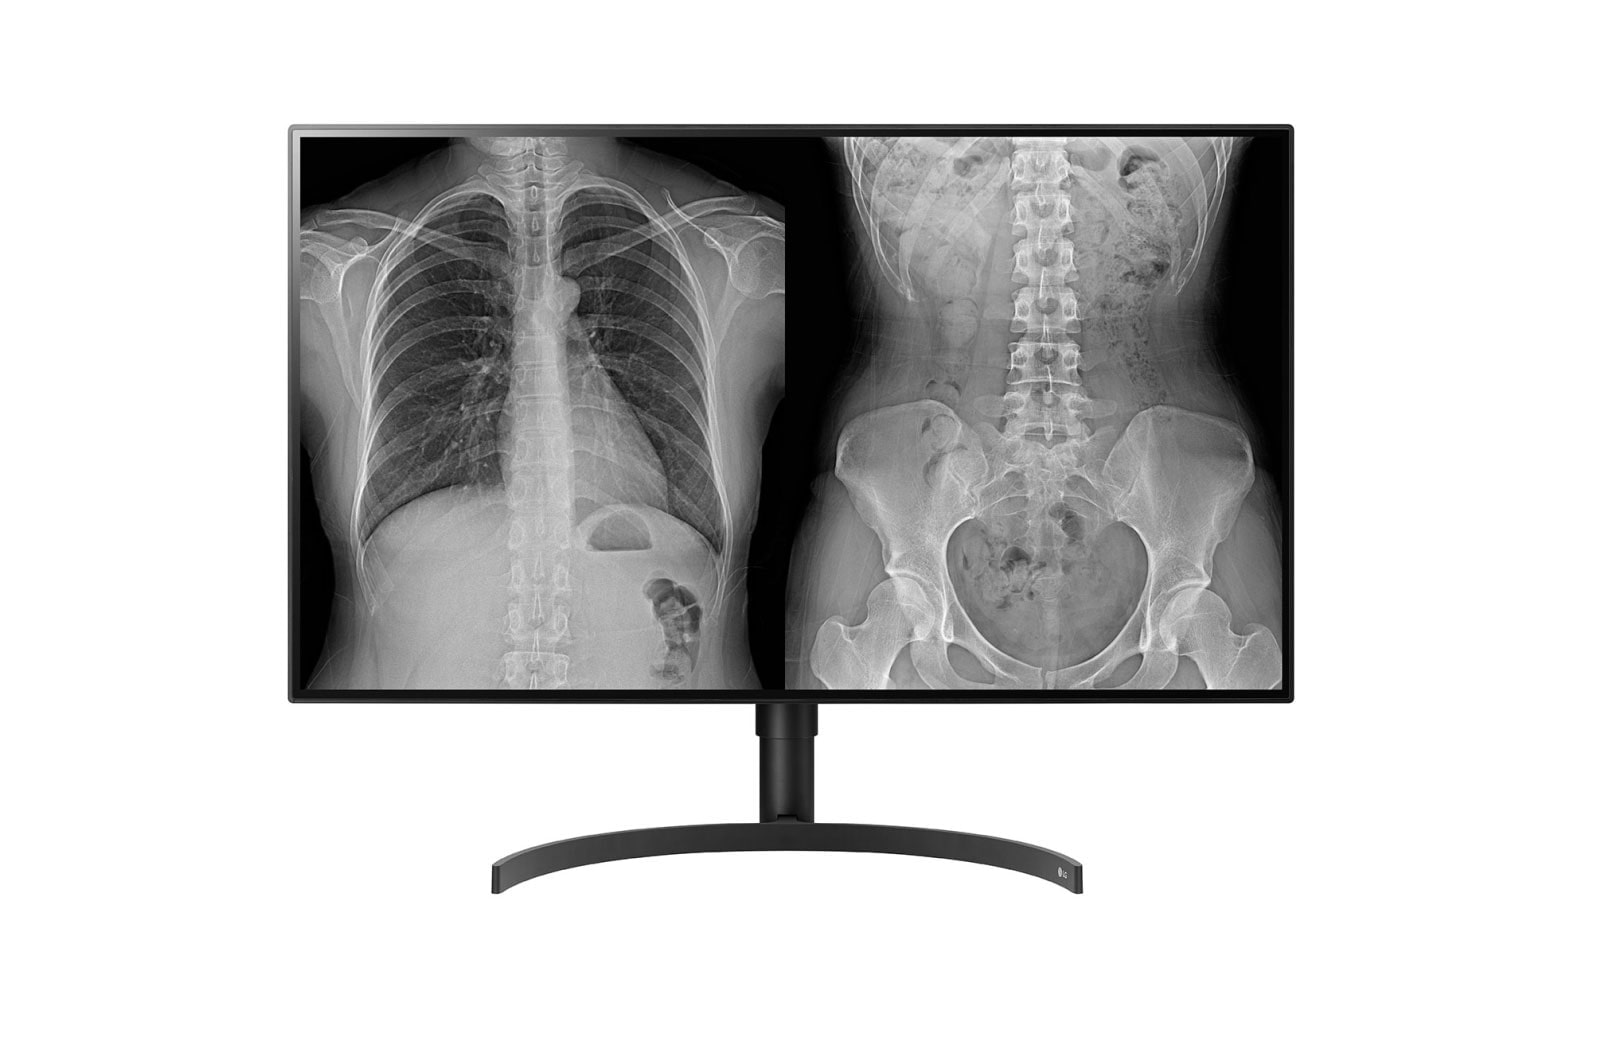

Monitor de Diagnóstico 32" 8MP

Monitor de Diagnóstico 32" 8MP

Calidad de imagen Optimizada para

Revisado Diagnóstico